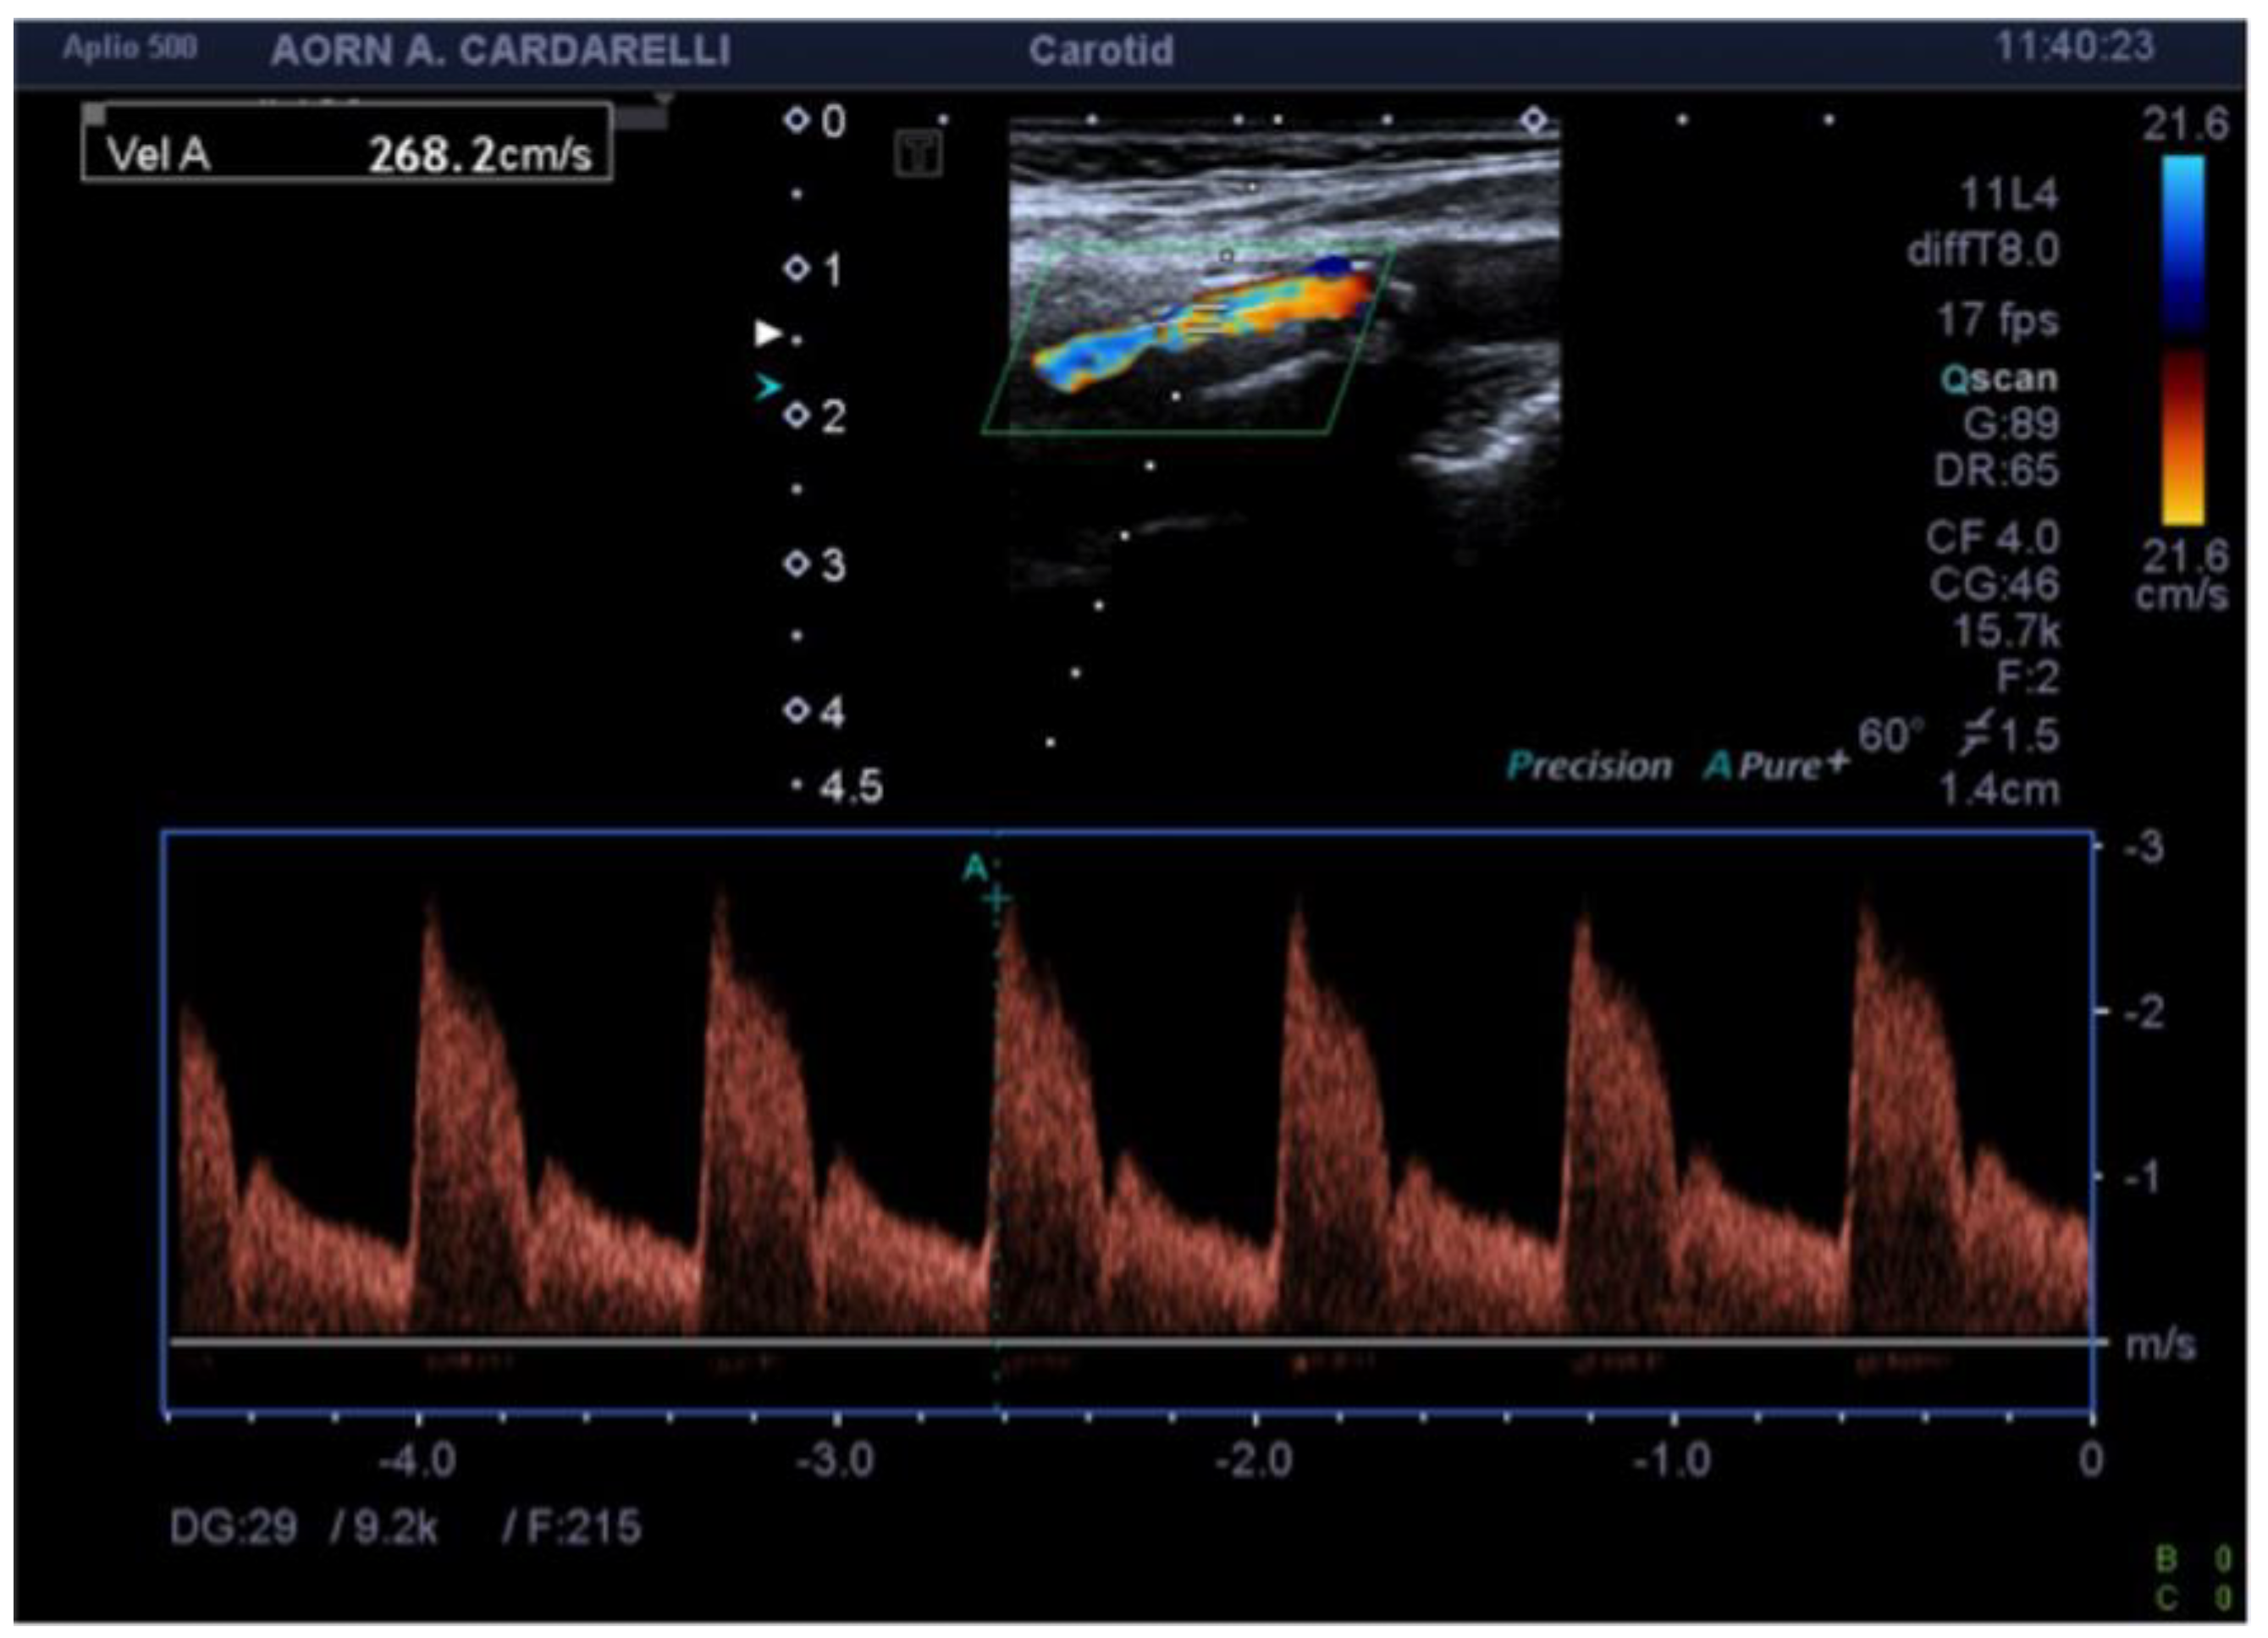

6. High Frame Rate Vector Flow (V-Flow) and 3D Arterial Analysis Ultrasound (3D-US)

- Qiu, Y.; Dong, Y.; Mao, F.; Zhang, Q.; Yang, D.; Chen, K.; Shi, S.; Zuo, D.; Tian, X.; Yu, L.; et al. High-Frame Rate Vector Flow Imaging Technique: Initial Application in Evaluating the Hemodynamic Changes of Carotid Stenosis Caused by Atherosclerosis. Front. Cardiovasc. Med. 2021, 8, 617391. [Google Scholar] [CrossRef] [PubMed]

- Yiu, B.Y.; Lai, S.S.; Yu, A.C. Vector projectile imaging: Time-resolved dynamic visualization of complex flow patterns. Ultrasound Med. Biol. 2014, 40, 2295–2309. [Google Scholar] [CrossRef]

- Zhang, X.; Yao, Z.Q.; Karuna, T.; He, X.Y.; Wang, X.M.; Li, X.F.; Liu, W.C.; Li, R.; Guo, S.Q.; Chen, Y.C.; et al. The role of wall shear stress in the parent artery as an independent variable in the formation status of anterior communicating artery aneurysms. Eur. Radiol. 2019, 29, 689–698. [Google Scholar] [CrossRef]